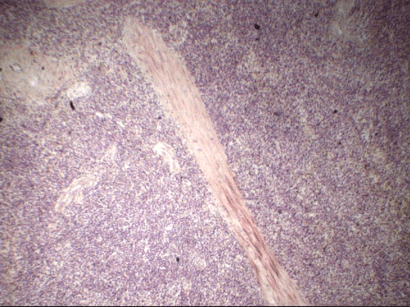

Препарат: Изменения в головном мозге при чуме свиней

Рис. 259. Изменения в головном мозге при чуме свиней

Изменения в центральной нервной системе при чуме свиней отмечают примерно в 70% случаев. В целом процесс характеризуется как острый негнойный энцефалит. От других вирусных энцефалитов он отличается тем, что при нем почти нет клеточных узелков. Просматривая под микроскопом срез из головного мозга, видно, что основной формой изменений являются периваскулярные клеточные инфильтраты. Они заполняют местами не только периваскулярные пространства, но распространяются и на прилегающую глию. Часто клетки инфильтрата неравномерно располагаются в периваскулярных пространствах, а иногда образуют резко выраженные муфты.

Изучая инфильтраты и муфты при большом увеличении микроскопа, отмечают, что они состоят из клеток лимфоидного типа и гистиоцитов, среди которых встречаются клетки с рексисом и пикнозом ядер. Наряду с периваскулитами изменения наблюдают и в стенках мелких сосудов, где можно видеть гиалинизацию и некроз их, а также набухание и пролиферацию эндотелия. Ганглиозные клетки поражаются главным образом в участках, где располагаются измененные кровеносные сосуды. Там наблюдают хроматолиз и вакуолизацию этих клеток, а также истинную и ложную нейронофагию.

Макроскопических изменений в центральной нервной системе обычно нет. Очень редко при вскрытии находят единичные кровоизлияния и незначительный отек головного мозга и его оболочек.